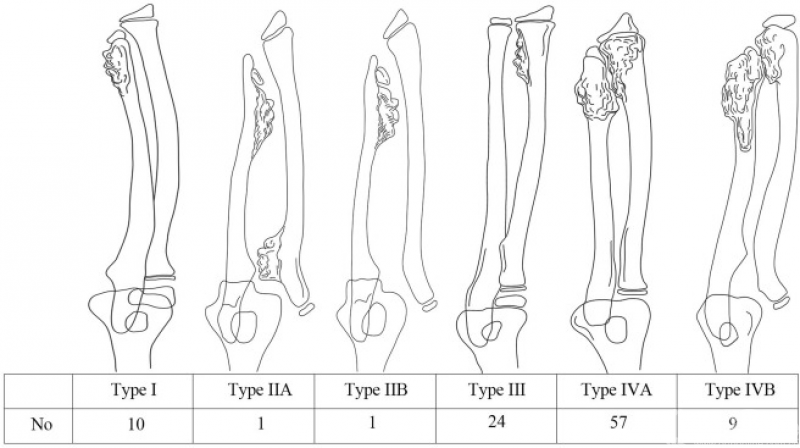

2017年,韩国学者Ah Reum Jo等基于Masada分型进行改良,新增了尺桡骨远端并存骨软骨瘤的IVa和IVb型(图3)。

图3. 改进的分型方案